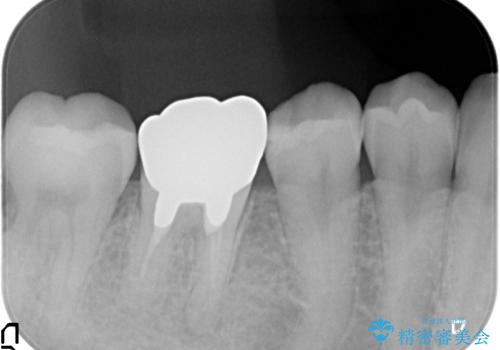

検査の結果右下6に根尖病変を認めたため、再根管治療を行いました。

その後症状の消失を確認し、オールセラミッククラウンによる補綴を行いました。